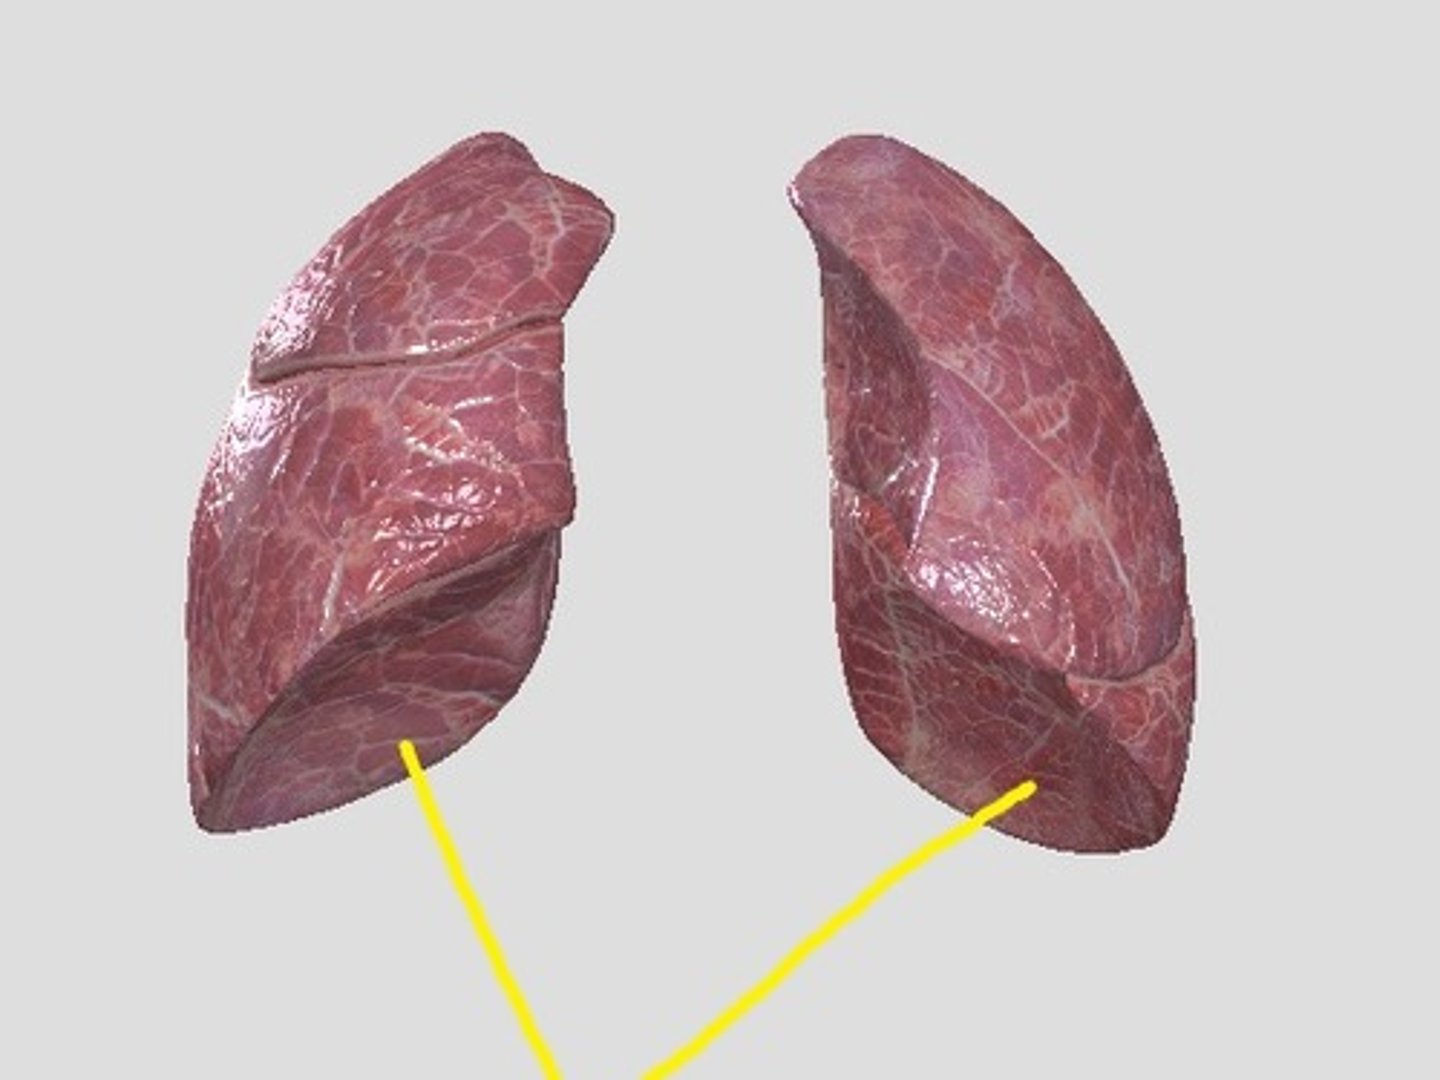

lung (normal)

smoker's lung

right lung

superior lobe of right lung

middle lobe of right lung

inferior lobe of right lung

left lung

superior lobe of left lung

inferior lobe of left lung

base (diaphragmatic surface)

apex

hilum of right lung

hilum of left lung